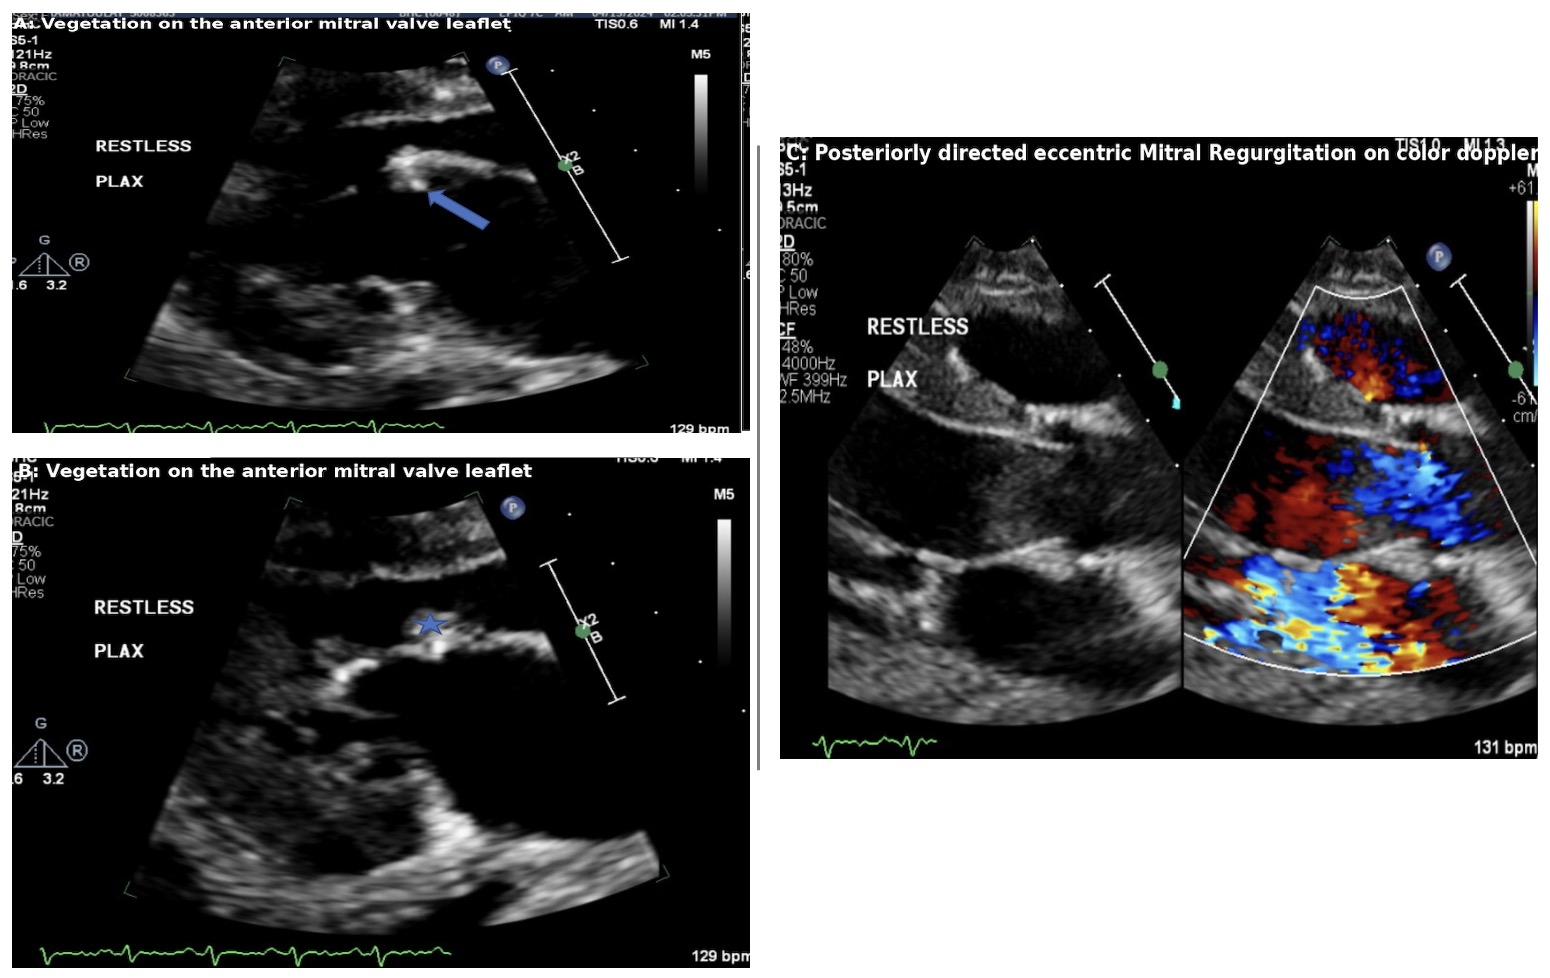

A 27-year-old woman from outside the United States, with no prior medical history, presented to the emergency room (ER) with fever and unresponsiveness. Upon arrival, she was found to have a basilar tip occlusion with multifocal posterior fossa infarcts. Imaging also revealed a subarachnoid hemorrhage, suspected to be secondary to a ruptured distal basilar aneurysm. The patient experienced associated seizures and acute hypoxic respiratory failure due to aspiration and bulbar weakness, necessitating an upgrade to the neuro-intensive care unit (ICU). Blood cultures drawn in the ER were positive for Streptococcus mitis/oralis. A transthoracic echocardiogram (TTE) showed a thickened mitral valve with a thick shaggy vegetation on the atrial side of the anterior mitral leaflet, as well as vegetation on the posterior leaflet and severe mitral regurgitation (MR). The patient was diagnosed with S. mitis mitral valve endocarditis. Due to the severity of her neurological and cardiac conditions, she was pending cardiothoracic (CT) intervention after stabilization in the neuro ICU.